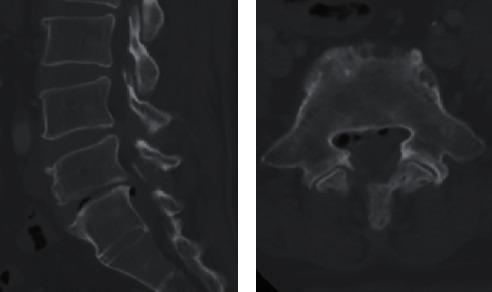

硬膜外气体聚集导致的腰椎神经根病

Lumbar Radiculopathy Caused by Epidural Gas Collection.

Degenerated intervertebral discs in the lumbar spine are commonly found with vacuum phenomenon. In a few cases, gas can migrate into the lumbar spinal canal and compress the nerve root. . We report a case of lumbar radiculopathy caused by epidural gas collection in a 59-year-old woman. Originally, the gas was formed in the intervertebral disc and possibly migrated backward because of the motion of lumbar spine, forming a single large gas formation. The nerve root was freed from the gas-filled cyst after needle puncture was performed. Patient's symptoms in the leg were significantly relieved following surgery.

CONCLUSION

There is still no satisfactory explanation for the pathogenesis of gas formation in the spinal canal. In our case, the presence of gas in the spinal canal and gas inside a narrowed disc suggests a communication between the two structures.

腰椎间盘退变时常见真空现象。少数情况下,气体可进入腰椎管并压迫神经根。我们报告一例59岁女性因硬膜外气体聚集导致的腰椎神经根病。最初,气体在椎间盘内形成,可能因腰椎运动而后移,形成单个大的气体团块。穿刺后神经根从充满气体的囊肿中松解出来。术后患者腿部症状明显缓解。

结论

椎管内气体形成的发病机制仍无令人满意的解释。在我们的病例中,椎管内气体和狭窄椎间盘内气体的存在提示这两个结构之间存在连通。